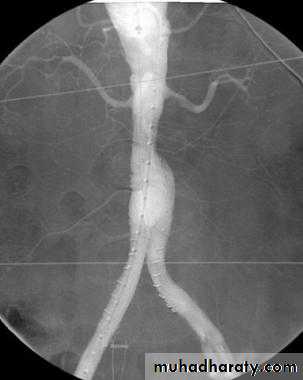

Angiography of abdominal aortic aneurysm